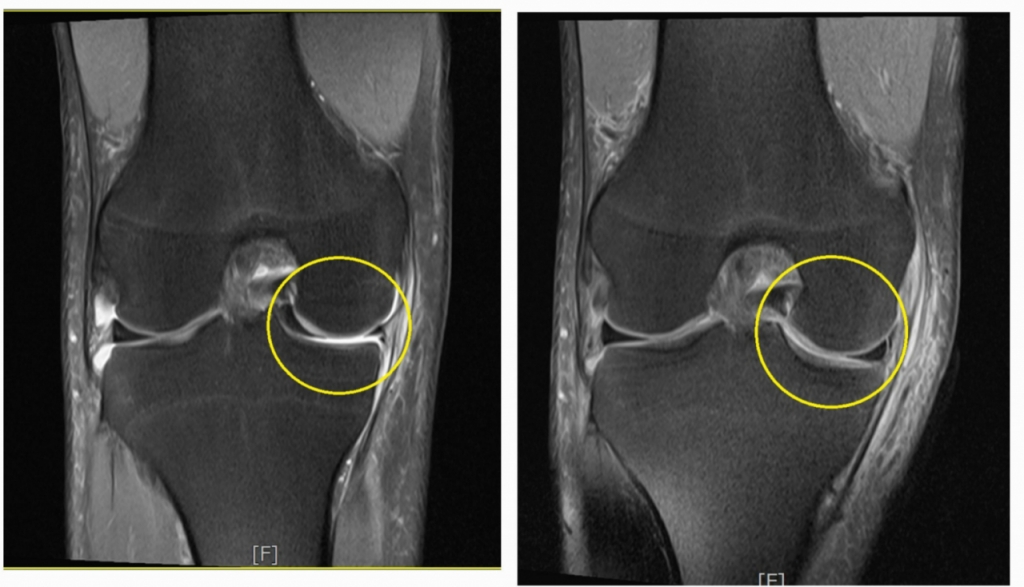

다소 생소한 이름의 반월상(반달 모양) 연골판은 허벅지 뼈와 정강이뼈 사이를 잇는 무릎 조직으로, 충격을 흡수할 뿐 아니라 연골의 접촉면을 넓혀 관절을 잘 움직이게 하는 역할을 한다. 스포츠 외상, 사고처럼 큰 충격을 받으면 손상당할 수 있다. 찢어진 연골판 조각이 관절 사이 껴 관절의 움직임을 방해하고 통증과 함께 무릎이 굽혀지지도 펴지지도 않는 잠김 현상이 나타나 환자들이 불편함을 크게 느끼기도 한다.

서울예스병원의 정현수 원장은 "반월상연골판 파열과 관절연골 손상의 경우, 그대로 방치하면 손상 범위가 넓어져 수술이 불가피하거나 무릎 퇴행성 관절염을 부추기는 원인이 될 수 있으므로 무릎이 불편하다면 바로 전문의의 진료를 받아야 한다"고 말했다. 특히 연골판 파열은 엑스레이 검사만으로 진단할 수 없으므로 자기공명영상(MRI)과 숙련된 전문의의 촉진 등 보다 정확한 검사를 병행하는 것이 현명하다고 정현수 원장은 강조했다.